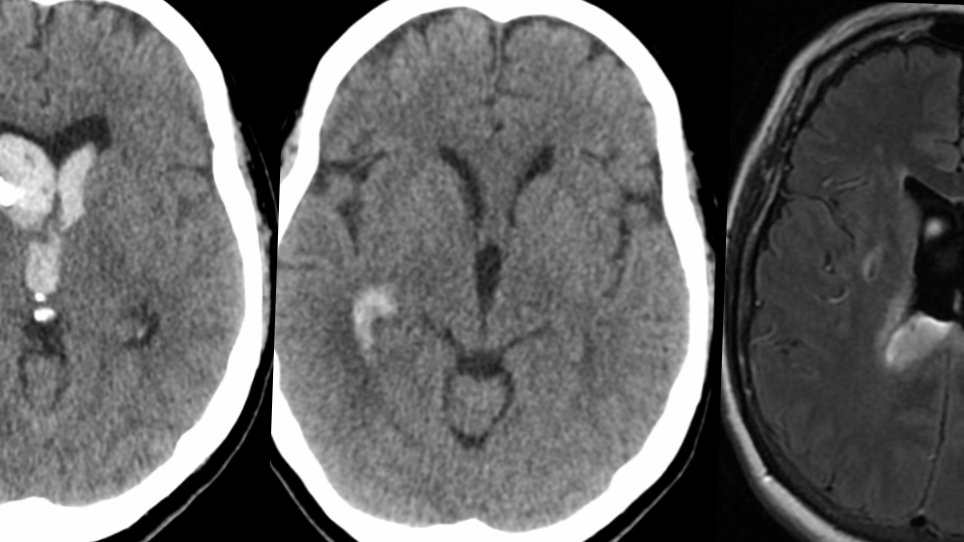

A black-and-white CT scan of a brain, showing three different cross-sectional views: axial, coronal, and sagittal, patient suffered from spontaneous ICH and intraventricular bleeding

• Subarachnoid hemorrhage (SAH) — bleeding into the cerebrospinal fluid spaces around the brain, often from a ruptured aneurysm.

• Intracerebral hemorrhage (ICH) — bleeding directly into the brain tissue.

• Intraventricular hemorrhage (IVH) — bleeding into the brain’s ventricular system, frequently complicating SAH or ICH.